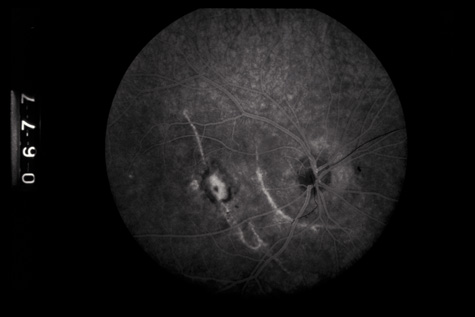

Commotio retinae (Latin, meaning retinal contusion) is a contrecoup injury. It can occur peripherally (Fig. 8) or centrally, in which case it is called Berlin's edema (Fig. 9). Immediately and for several hours after the trauma, the retina appears normal, although the patient may complain of decreased vision. Thereafter, the outer layers of affected retina become opaque. On fluorescein angiography, the opaque retina blocks background choroidal fluorescence, and in most cases there is no leakage into or under the retina (Fig. 10). For years, clinicians had difficulty explaining this blockage, because leakage is expected in conditions with edema. It was then shown in experimental animals and in human autopsy eyes that Berlin's edema is not true edema. The retinal opaqueness is the result of intracellular edema and fragmentation of the photoreceptor outer segments and intracellular edema of the underlying pigment epithelium. There is little or no intercellular fluid.66–69

Fig. 10. A: Commotio retinae in the macula. B: On the angiogram there is no leakage in the area of commotio retinae.